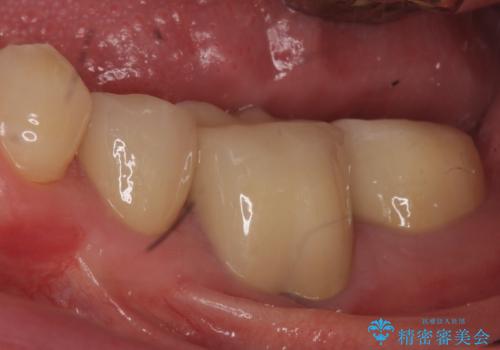

- 上の前歯は内側に入っていることが気になりご相談にいらした方です。インビザラインにて治療を行いました。

1週間でのマウスピース交換を指示していましたが、20時間以上使えない時があると不安との事で、2週間ごとの交換にしていました(実際はほとんど20時間以上使用できていたようです)。治療終了まで時間はかかりましたが、最終的に綺麗に並べることができ、大変喜んでいただけました。